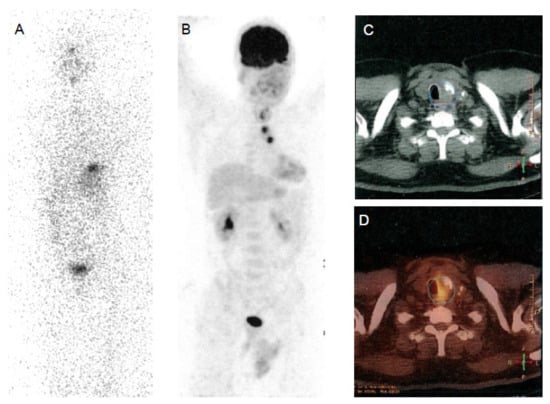

Figure 3.

A 76-year-old patient with prostate cancer and a right thyroid nodule of 15 mm in diameter. Multiple image projections (A), fusion PET-CT images (B), CT images (C) and PET images (D), respectively, of 68Ga-PSMA imaging with high-intensity PSMA accumulation. Fine needle aspiration biopsy of PSMA-avid thyroid lesion was performed revealing an indeterminate cytology. Final histology revealed papillary thyroid cancer.